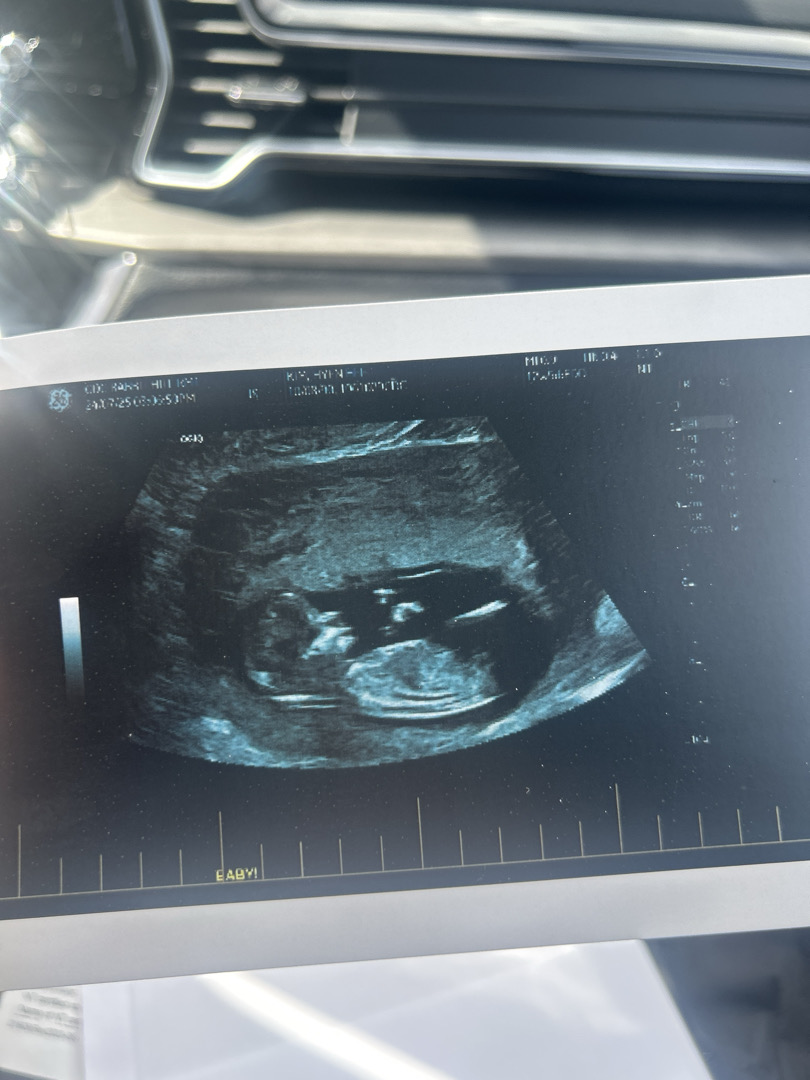

12주 5일차 각도법 봐주세요.

선생님들 많은 의견 부탁드려요!!